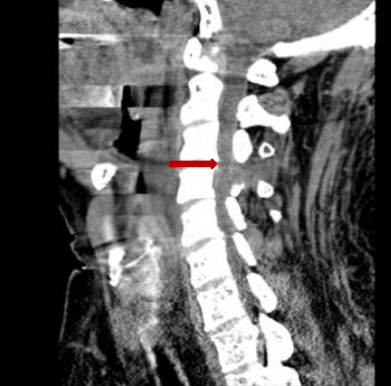

颈后路术后颈椎CT。

后入路术后见颈部椎管后方减压范围满意,骨性结构破坏小。